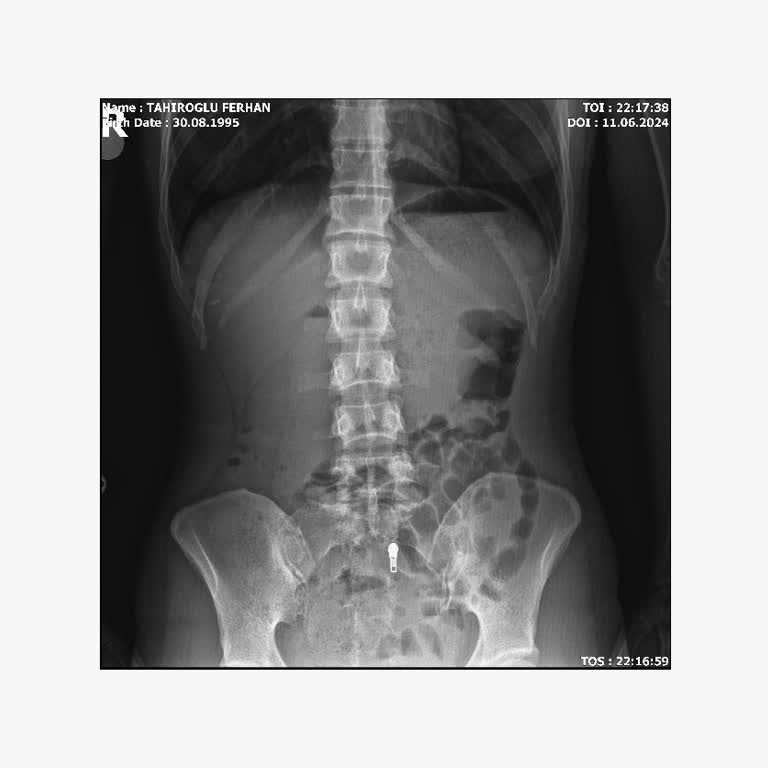

Ailemin memnuniyeti doğrultusunda bu yıl özel sağlık sigortamı Allianz Sigorta üzerinden yaptırdım; ancak yaşadığım süreç beni ciddi şekilde hayal kırıklığına uğrattı. 9 Şubat tarihinde gıda zehirlenmesi şikayetiyle Maltepe Tıp Fakültesi Hastanesi’ne başvurdum. Muayene sırasında tansiyonumun yüksek...